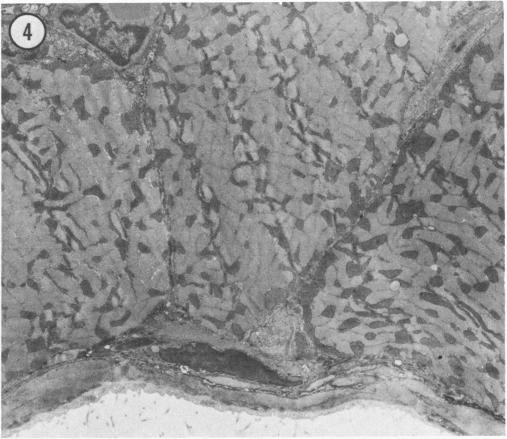

In this study, the authors examined the effect of the anti-tumor agent Adriamycin, a known cardiotoxin, on mouse heart, diaphragm, and gastrocnemius muscle. Using an established model of Adriamycin cardiac toxicity, they found that 4 days after the intraperitoneal injection of 20 mg/kg of Adriamycin, characteristic heart lesions, including vacuolation of the sarcoplasmic reticulum, interstitial edema, and mitochondrial degeneration, were demonstrated in all treated animals. Furthermore, similar, but much more severe, myocyte damage was demonstrated in the diaphragm; muscle toxicity followed a decreasing gradient of injury from the peritoneal to the thoracic surface of the tissue. On the other hand, treatment with Adriamycin resulted in an increase in the size and number of lipid droplets in the red fibers of the gastrocnemius muscle without any other ultrastructural evidence of drug-induced damage to myocytes. An examination of the pharmacokinetics and metabolism of Adriamycin after intraperitoneal treatment revealed that relative drug levels in muscle (diaphragm much greater than heart much greater than gastrocnemius) paralleled the degree of ultrastructural damage observed. This study indicates that treatment with Adriamycin can produce significant injury to non-cardiac muscle in a fashion that strongly resembles the characteristic pattern of Adriamycin-related damage to the heart, and that the degree of myocyte damage is apparently dependent upon the Adriamycin concentration in the tissue.

在本研究中,作者研究了抗肿瘤药物阿霉素(一种已知的心脏毒素)对小鼠心脏、膈肌和腓肠肌的影响。他们使用已建立的阿霉素心脏毒性模型,发现腹腔注射20mg/kg阿霉素4天后,所有接受治疗的动物均出现了特征性的心脏病变,包括肌浆网空泡化、间质水肿和线粒体变性。此外,在膈肌中也发现了类似但更为严重的心肌细胞损伤;肌肉毒性从组织的腹膜面向胸表面呈现递减的损伤梯度。另一方面,阿霉素治疗导致腓肠肌红色纤维中脂滴的大小和数量增加,而没有任何其他药物诱导的心肌细胞损伤的超微结构证据。对腹腔注射阿霉素后的药代动力学和代谢进行检查发现,肌肉中的相对药物水平(膈肌远高于心脏,心脏远高于腓肠肌)与观察到的超微结构损伤程度平行。这项研究表明,阿霉素治疗可对非心肌产生显著损伤,其方式与阿霉素相关的心脏损伤特征模式极为相似,并且心肌细胞损伤程度显然取决于组织中阿霉素的浓度。